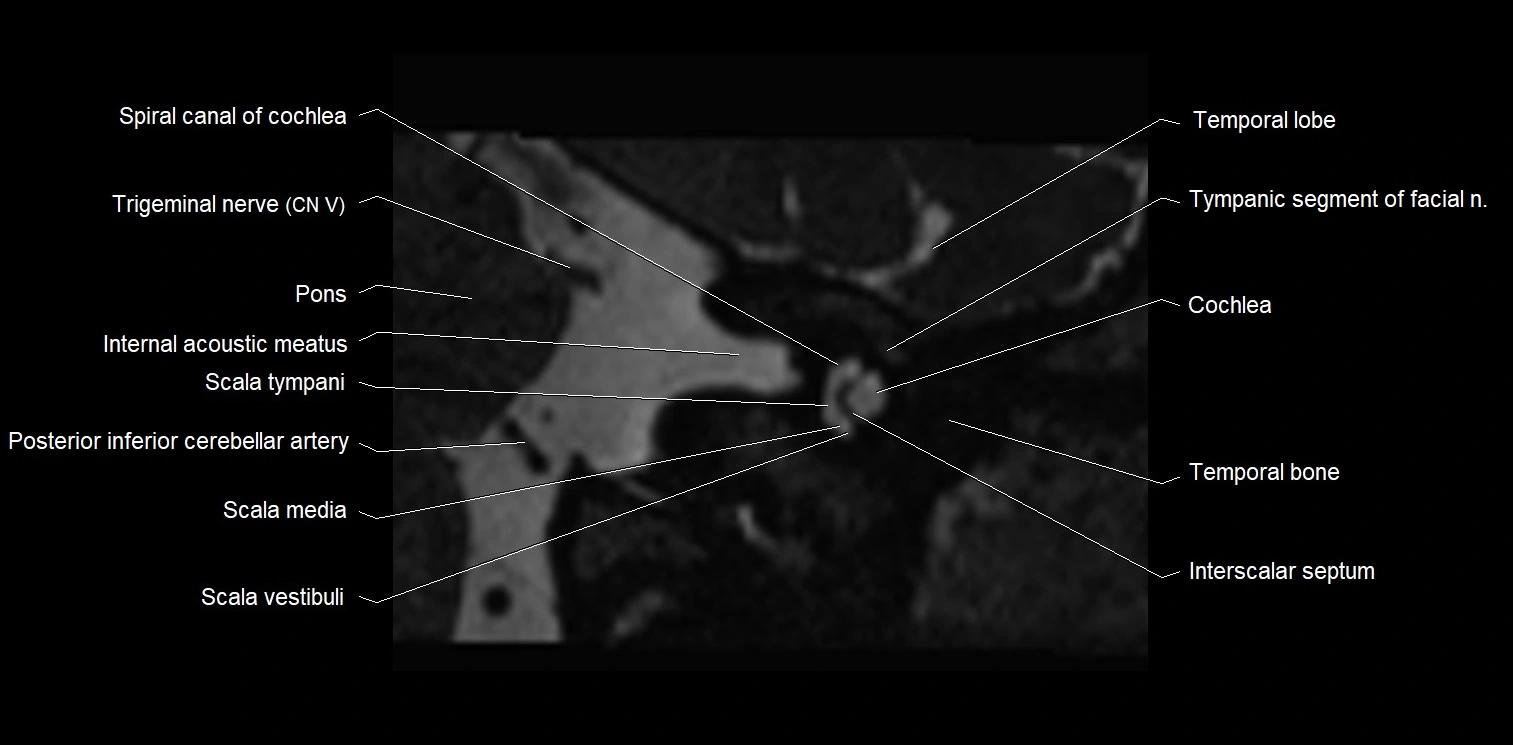

MRI Appearance

• The abducens nerve is a small, thin, linear structure

• Best visualized on high-resolution T2-weighted 3D MRI sequences (e.g., FIESTA or CISS)

• Seen as a hypointense (dark) line running from the brainstem at the pontomedullary junction, traversing the prepontine cistern, and entering Dorello’s canal under the petrosphenoidal ligament, then into the cavernous sinus, and finally the orbit

• May be challenging to visualize in standard MRI due to its small size

• Pathology may be inferred by absence, displacement, or enhancement of the nerve